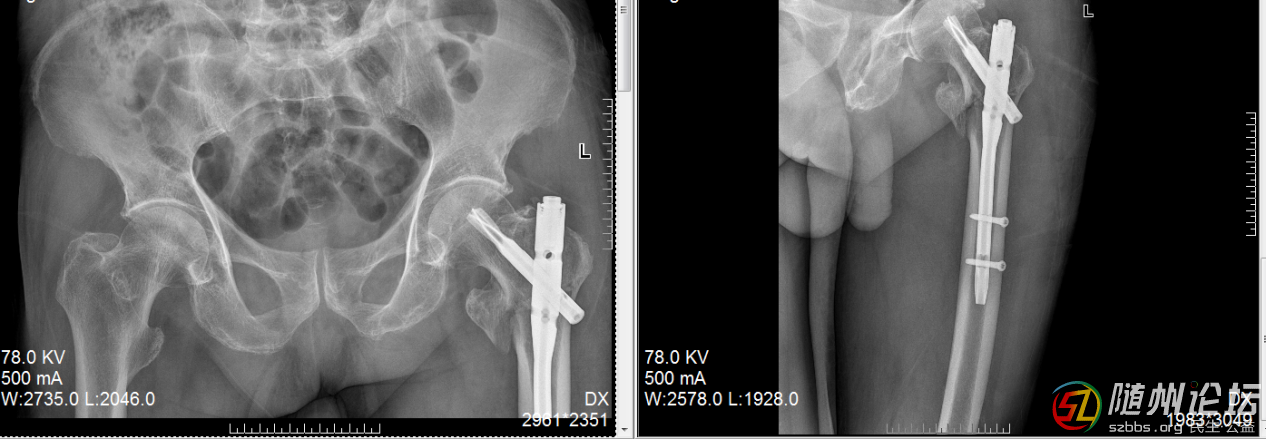

另一位送錦旗的,是一位年過八十的老奶奶,她不慎摔傷了髖部。考慮到患者年紀(jì)大、基礎(chǔ)疾病多,創(chuàng)傷骨科啟動多學(xué)科會診(MDT),為其制定了完全個性化的手術(shù)及康復(fù)方案。沒有采用“一刀切”的模式,而是綜合評估其身體狀況、生活需求及家庭支持,選擇了創(chuàng)傷最小、最適合的微創(chuàng)髓內(nèi)釘固定,并結(jié)合中西醫(yī)結(jié)合的康復(fù)理念,術(shù)后早期運用中藥熏蒸等手段活血化瘀、消腫止痛。術(shù)后早期功能鍛煉,顯著改善了患者的舒適度,縮短了臥床時間,有效預(yù)防了并發(fā)癥,讓老人能重新站立行走。